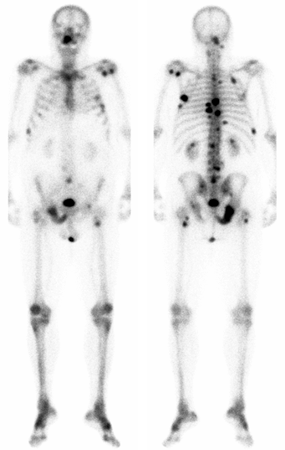

Skjelettscintigrafi av pasient med prostatakreft.

Bilde forfra til venstre og bakfra til høyre. De mørke feltene på bildet antyder skjelettmetastaser.